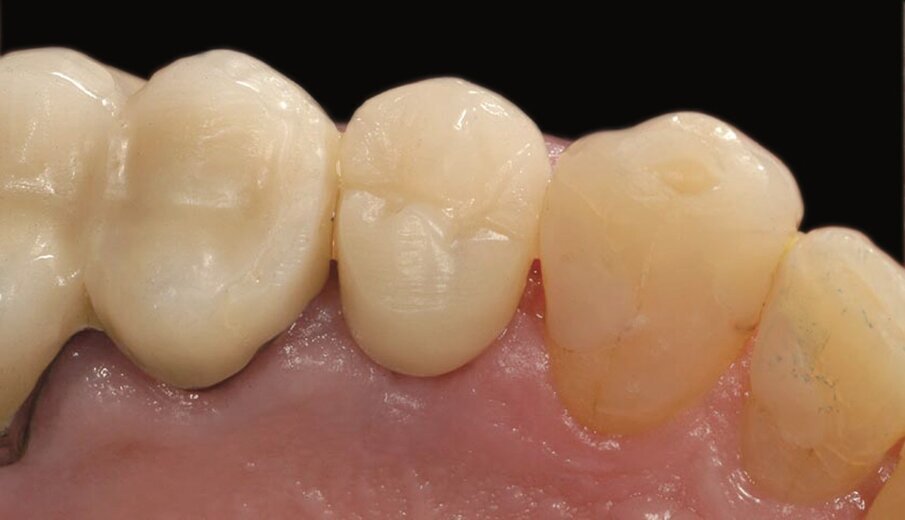

Fig. 2c_Fase protesica provvisoria libera da contatti occlusali.